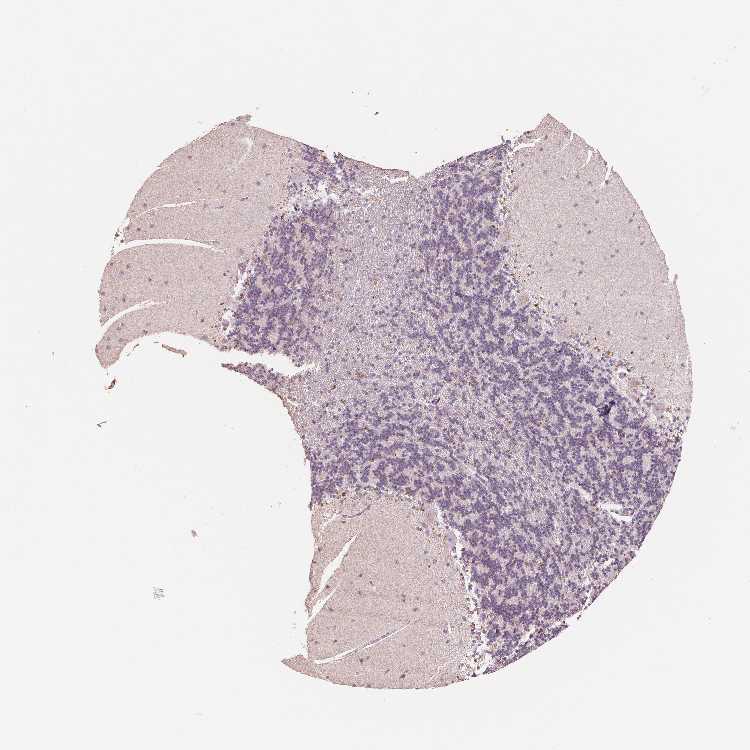

BRAIN CEREBELLUM Show tissue menu

CEREBELLUM - Expression summary

CEREBELLUM - Antibody stainingi

Antibody staining in the annotated cell types in the current human tissue is reported as not detected, low, medium, or high, based on conventional immunohistochemistry profiling in selected tissues. This score is based on the combination of the staining intensity and fraction of stained cells.

Each image is clickable and will lead to virtual microscopy that enables deeper exploration of all samples and also displays staining intensity scores, fraction scores and subcellular localization as well as patient and tissue information for each sample.

Antibody HPA063240Antibody HPA064557

Purkinje cells MediumNot detected

Cells in granular layer Not detectedNot detected

Cells in molecular layer Not detectedNot detected